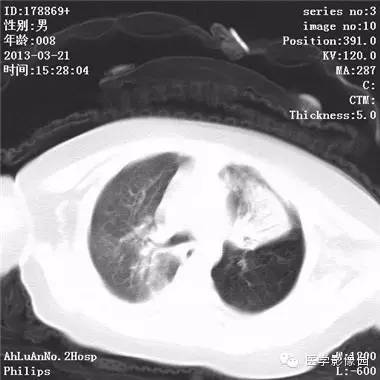

【病例】支气管异物1例CT影像表现

患儿男,8个月,呛咳,发热一周。实验室检查白细胞及中性粒细胞增高。

两肺肺纹理增多、增粗,右肺可见斑片状、片絮状模糊影,边界欠清;左肺上叶见楔形高密度影,内可见支气管征,尖端指向肺门;左肺下叶肺野透亮度增强;另见左肺主支气管内可见块状软组织密度影。

支气管异物(花生米)伴两肺炎症(追问病史,患儿奶奶层于一周前喂食患儿花生米,当时疑似“呛进去”,后来见好了也就没留意)。